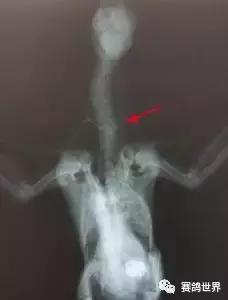

给鸽子注射止痛药和抗炎药。拍摄X射线(X射线),他们清楚地表明,这只鸟确实有颈部的压缩性骨折,所以我们可以排除副粘病毒和中毒。我们永远不会知道这羽鸽子是在第一次尝试从巢中飞行,在下面的人行道上不正确着陆,还是如果她已经在人行道上休息,一个路人造成了她的伤害。